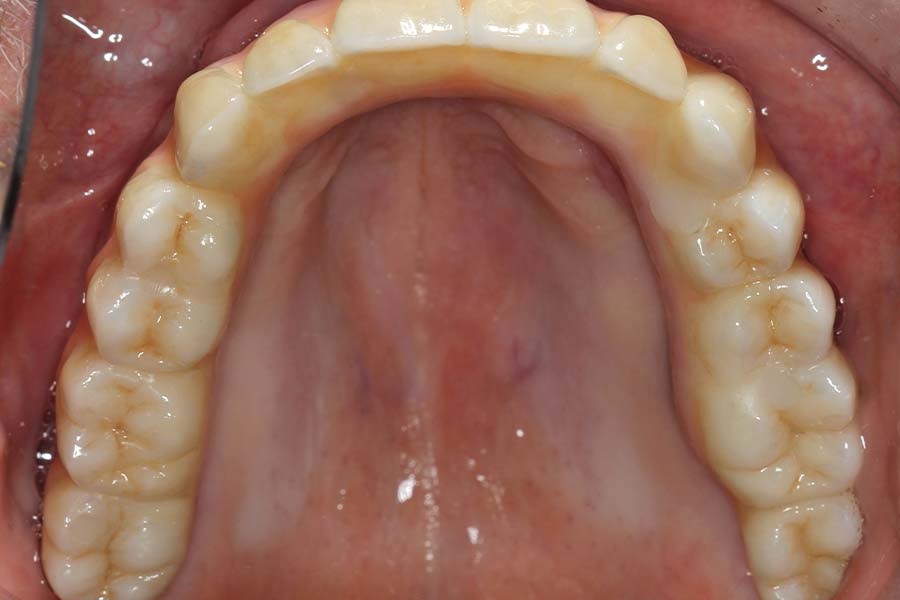

Wax try-in of upper final prosthesis. Nothing is left to chance, we try this in for evaluation of aesthetics, bite, smile and patient approval.